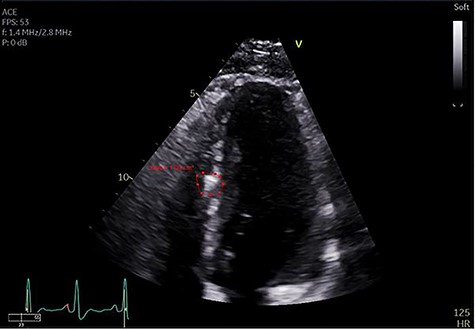

Echocardiogram identifying bullet fragment in the interventricular septum.

The patient recovered without complications other than a persistent, asymptomatic, sinus tachycardia with heart rate sustained at 120 beats per minute. On post-trauma Day 10 an echocardiogram was obtained, which again demonstrated two bullet fragments retained within the interventricular septum, a small pericardial effusion without evidence of tamponade and no evidence of ventricular septal defect (Fig. 3). Non-operative management of the retained septal projectiles was pursued. Empiric colchicine 0.6 mg twice daily for post-traumatic pericarditis prophylaxis was prescribed. Four days later the patient’s tachycardia resolved spontaneously. Point of care ultrasound demonstrated resolution of the pericardial effusion. The patient was discharged from the hospital on post-trauma Day 19 with a 2-month course of colchicine. At outpatient follow-up, he continued to maintain normal sinus rhythm without evidence of effusion or pericarditis.